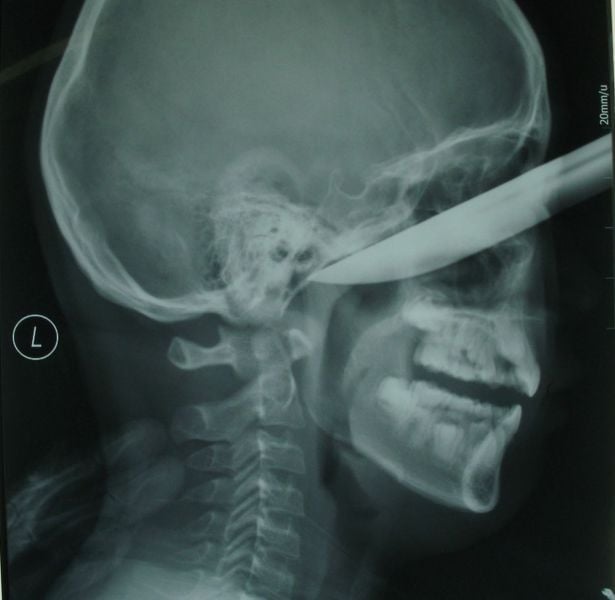

A 16-year-old cheated death when a 5-inch knife was plunged into his head. The teenager was rushed to hospital with the kitchen knife still stuck in his forehead.